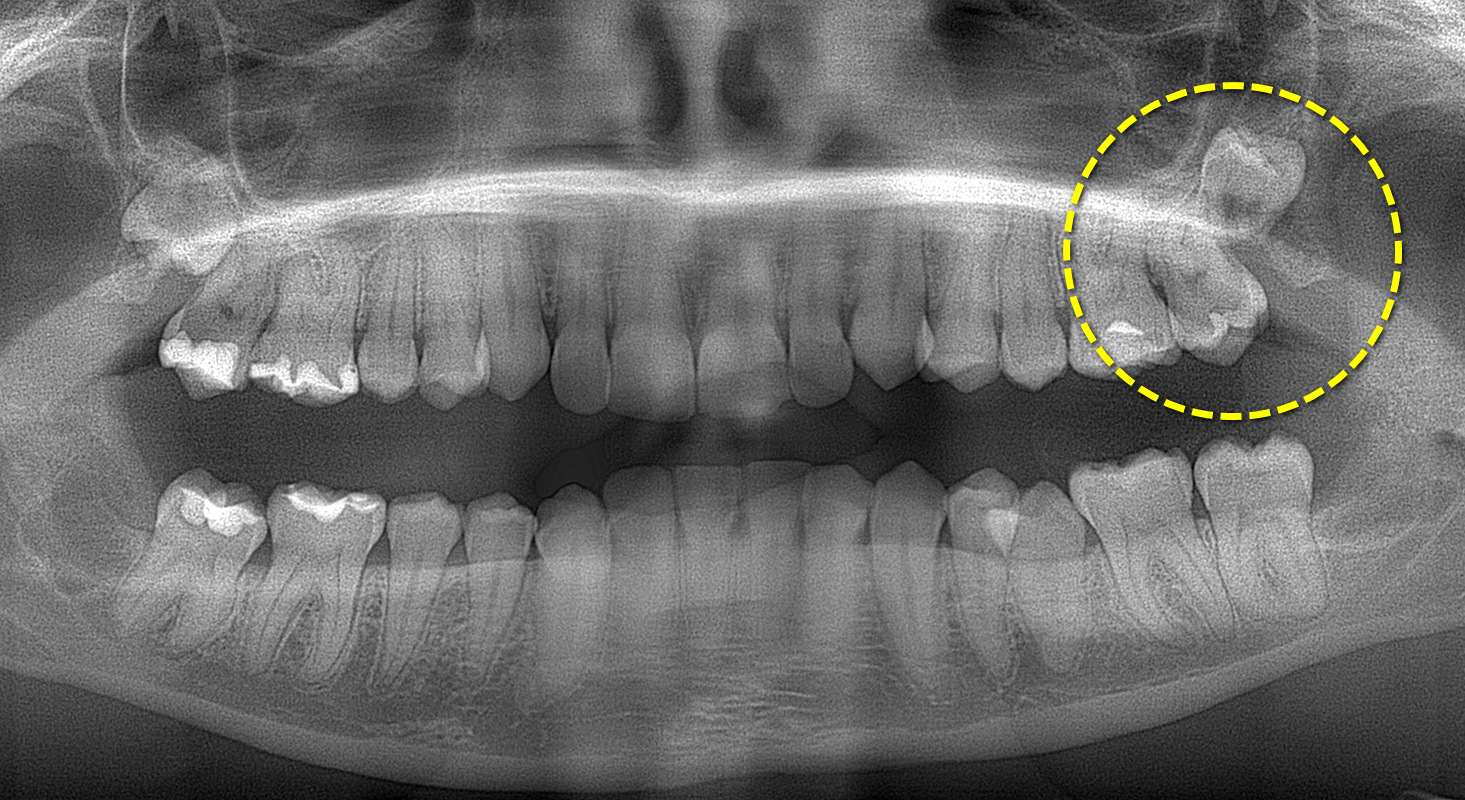

Головний різновид – складне видалення зуба мудрості. Ці маніпуляції проводяться тільки після комплексної діагностики та призначення стоматолога. Метод втручання залежить від розташування зуба мудрості, кількості коренів і типу патології. Видалення верхніх вісімок зазвичай проходить легше, зважаючи на меншу товщину кістки, якщо порівнювати з нижньої щелепою. Крім того, набагато частіше трапляється дистопія та ретенція саме нижніх зубів мудрості. Вони можуть бути частково чи повністю занурені в ясна, прорізуватися під кутом чи рости горизонтально в напрямку сусідніх молярів.